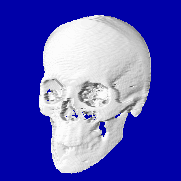

Это конфигурация для работы с изображениями. На рисунке видны два главных окна системы: окно Управление (справа) и окно Изображения, с изображением среза, полученного на рентгеновском томографе.